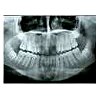

Ортопантомография. Это рентгенологическое исследование всех зубов и тканей верхней и нижней челюсти. Это позволяет диагностировать аномалии зубов и искривление зубов, состояние тканей пародонта, глубину полости зуба, утечку пломб, скрытый кариес, состояние челюсти в месте удаления зуба. Снимок зубной системы сделан ортопантомографом. Лучевая нагрузка при выполнении ортопантомограммы меньше, чем при рентгенографии внутренних органов. Существует фильм с ортопантомографией, представляющий традиционное изображение, и цифровая ортопантомограмма, данные которой хранятся в электронном виде.

С помощью рентгеновского панорамного изображения - ортопантомограммы - получается обзор структур как челюсти, так и височно-нижнечелюстных суставов. При оценке ортопантомограмм изображение зубного ряда и челюсти, связь между синусовым гаймарисом и нижнечелюстным нервом, наличие скрытого кариеса, состояние пломб, точность заполнения каналов, патологические изменения тканей пародонта, состояние Костная ткань после удаления зуба, сохранение и высота костных отверстий с учетом заболеваний пародонта и мн. Ортопантомограмма является важным методом диагностики при посещении стоматолога, врачей общей практики, периодонтологов, хирургов, ортопедов, ортодонтов и имплантологов. Ортопантомограммы без ухудшения здоровья могут выполняться чаще ежегодно и при необходимости.

На высококачественной ортопантомограмме закрытые челюсти выглядят «улыбающимися»: в то же время края зубного ряда слегка приподняты. С помощью ортопантомограммы формируется объективный вид зубочелюстного аппарата пациента. На ортопантомограмме отражаются все сформированные зубы, рудименты, дополнительные зубы, их форма, количество и расположение в кости, а также параллельность корней. На основании ортопантомограммы обнаружены неосложненный и осложненный кариес, скрытые кариозные полости и другие очаги одонтогенной инфекции; состояние уплотнений и каналов. Через изучение orthopantomograms, опытный специалист определит изменения в опорном аппарате зубов (пародонта), кости, височно-нижнечелюстных суставов, груди носа.